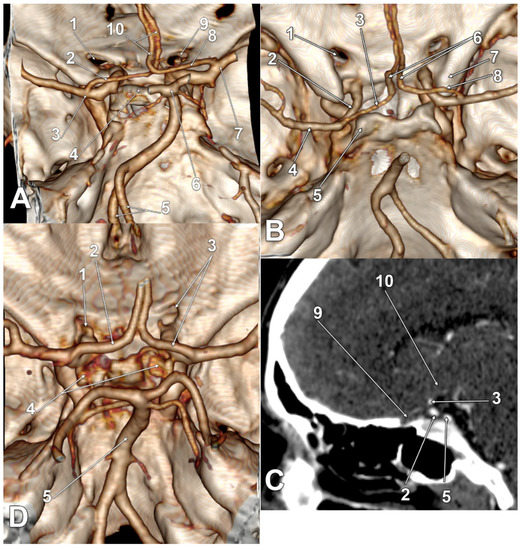

| Gender | Right Side | Left Side | Other Variations | Figure |

|---|---|---|---|---|

| M | type 3 IO A1 SCar | type 3 IO A1 SCar | high BA bifurcation | Figure 3A |

| M | type 3 IO A1 | type 3 IO A1 | Figure 2D | |

| M | type 2 IO A1 | type 1 IO A1 SCar | fenestrated AComA, hypoplastic left A1 | Figure 2A |

| M | type 2 IO A1 | type 2 IO A1 SCar | Figure 4C | |

| M | type 2 IO A1 | type 2 IO A1 | Figure 4A | |

| M | type 2 IO A1 | type 2 IO A1 | – | |

| M | type 2 IO A1 | type 2 IO A1 | Figure 5B | |

| F | type 2 IO A1 | type 2 IO A1 | rotated BA, left PCA displaced towards the ipsilateral A1 ACA | Figure 4D |

| F | type 2 IO A1 | type 2 IO A1 | duplicated AComA | Figure 4B |

| F | type 2 IO A1 SCar SClin | type 1 IO A1 | supraclinoid right A1 | Figure 2C |

| F | type 2 IO A1 | type 2 IO A1 | Figure 3D | |

| F | type 2 IO A1 | type 2 IO A1 | Figure 3B,C | |

| F | type 2 IO A1 | type 2 IO A1 | hypoplastic right A1 | |

| F | type 2 IO A1 SCar | type 2 IO A1 SCar | rotated AComA, hypoplastic right A1 | Figure 5A |

| F | type 2 IO A1 | type 2 IO A1 | rotated BA, left PCA displaced towards the ipsilateral A1 ACA | Figure 5C |

| F | type 1 IO A1 | type 2 IO A1 | left bihemispheric ACA | Figure 2B |